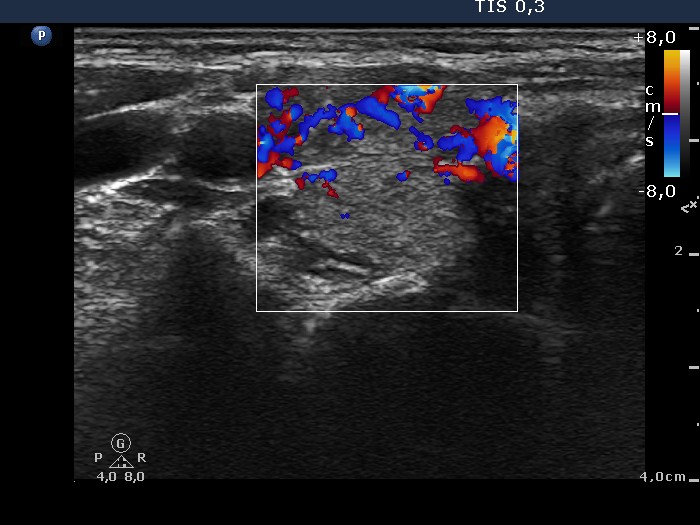

Graves' disease - Case 15.

Follow-up investigation 33 months after first visit (ultrasonographic picture 3)

Patient on daily 20 mg methimazole therapy in euthyroid state

Right lobe, horizontal scan, color Doppler mode. The vascularization is already more pronounced than the average but decreased compared with previous investigation.